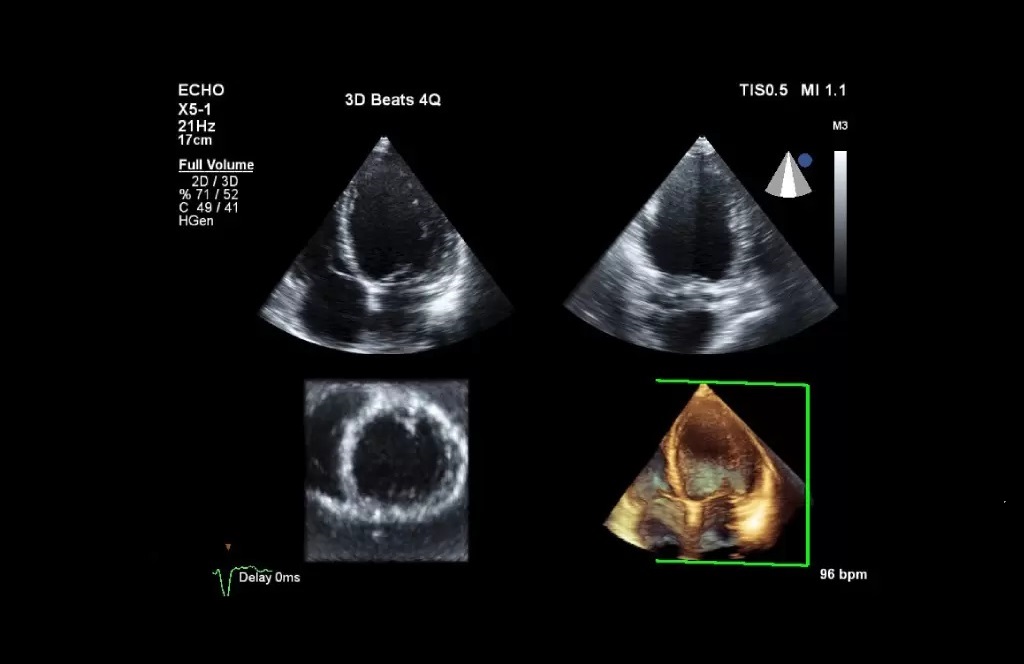

Cu ajutorul ecocardiografiei, evaluam dimensiunile celor patru cavități ale inimii și pereții acestora, principalele vase de sânge ce ajung și pleacă de la inimă, structura și modul de funcționare ale valvelor cardiace, pericardul (foița care învelește inima). De asemenea, se pot depista malformațiile cardiace sau existența tumorilor cardiace sau a infecțiilor la nivelul inimii.

Pe date legate de structură, ecocardiografia ne aduce informații legate și de funcția de pompă a inimii. Uneori, este nevoie ecocardiografii mai complexe, prin care urmărim performanța cardiacă, și atunci supunem inima unui stres, fie fizic (efort prin pedalarea pe un cicloergometru) fie farmacologic

(administrare unor substanțe care tahicardizează inima), scopul acestora fiind atât diagnostic cât și în stabilirea oportunitatii eventualelor terapii invazive.